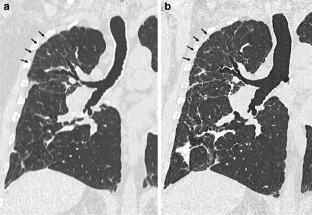

Fig. 4